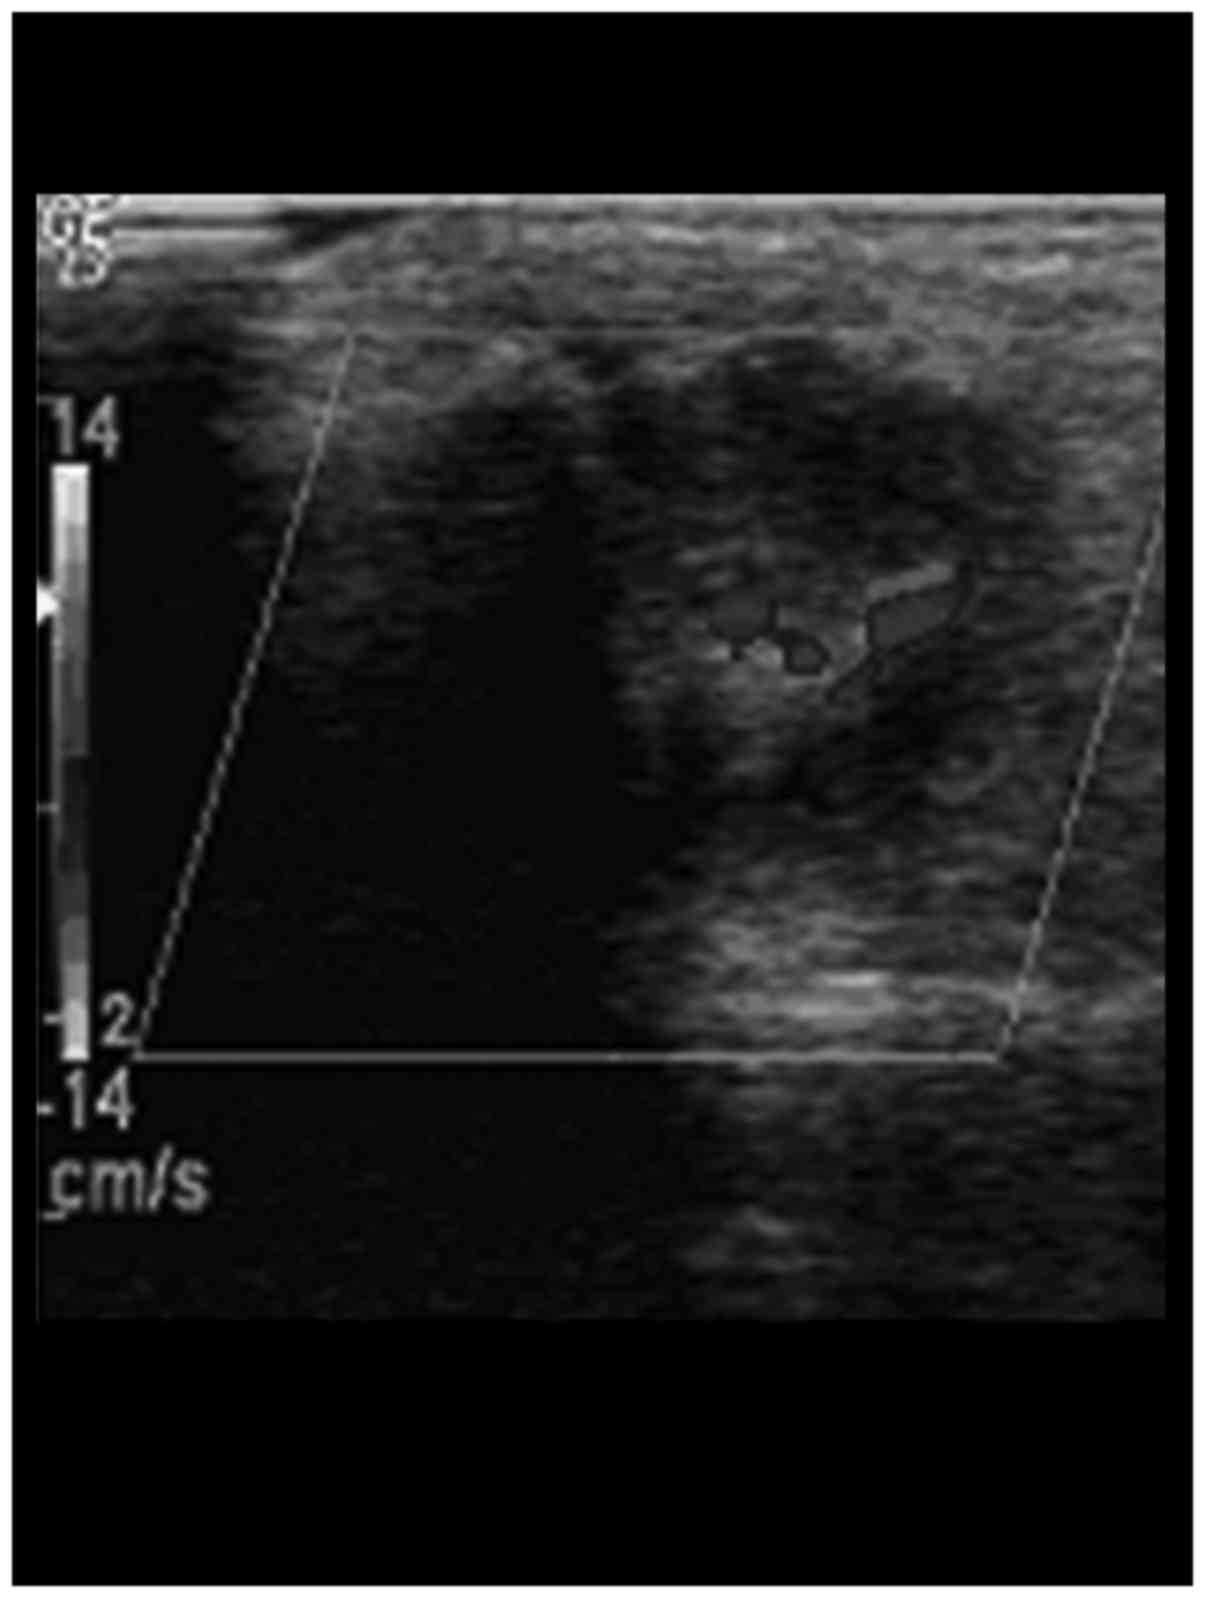

HCDU examination results showed that the articulationes interphalangeae of digitus medius in patients with bone erosion in the study group showed articular surface roughness, and continuous interruption at the margins (Fig. 1). The detectable blood signal rate of articulationes interphalangeae in the study group was 65.7%, and blood signals were detected inside the articulationes interphalangeae and at the margins (Fig. 2). The eroded cartilage and subcortex medullary bone substance in the study group had lower echogenicity and irregularly defined tumor-like lesion. The internal echo was uneven (Table I).

Figure 2.

The high-frequency color Doppler ultrasonography manifestation of the apterium blood of the articulationes interphalangeae of digitus medius of the patients with bone erosion.